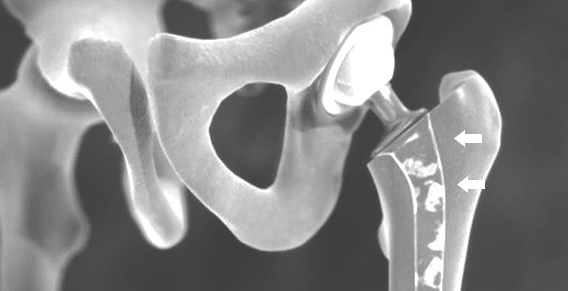

IN THE HIP JOINT, IN PARTICULAR INFECTION of the prosthesis material , EARLY SINTERING OF THE SHAFT or a fracture of the bone involving the implants are feared complications.

OFT can be re-operated with a primary hip implant when replacing the prosthesis. Sometimes special revision implants are also necessary.